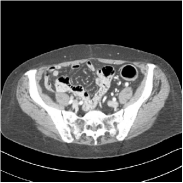

Refer to caption FBPRMSE = 194.09 HURefer to caption FBPRMSE = 194.09 HURefer to caption PWLS-ULTRARMSE = 43.40 HURefer to caption PWLS-ULTRARMSE = 43.40 HU

Refer to caption FBPConvNetRMSE = 34.24 HURefer to caption FBPConvNetRMSE = 34.24 HURefer to caption SUPER-FCN-DataTermRMSE = 31.21 HURefer to caption SUPER-FCN-DataTermRMSE = 31.21 HU

Refer to caption SUPER-FCN-ULTRARMSE = 28.82 HURefer to caption SUPER-FCN-ULTRARMSE = 28.82 HURefer to caption ReferenceRefer to caption Reference

Figure 5: Reconstructed images of slice 150 of patient L192 using of FBP, PWLS-ULTRA, FBPConvNet, SUPER-FCN-DataTerm, and SUPER-FCN-ULTRA, respectively, shown along with the reference.

Fig. 5 shows reconstructions using FBPConvNet, SUPER-FCN-DataTerm (i.e., β=μ=0𝛽𝜇0\beta=\mu=0), PWLS-ULTRA, and SUPER-FCN-ULTRA, respectively. For SUPER-FCN-DataTerm, when optimizing the data-fidelity term, we start with the deep network’s output and ran 5 iterations for the data-fidelity term to avoid overfitting to the analytical FBP images. In Fig. 5, obviously, FBPConvNet significantly suppresses noise and artifacts compared to PWLS-ULTRA, but it also over-smooths many details (e.g., features in the zoom-in box) in the reconstruction. SUPER-FCN-DataTerm, by enforcing data consistency, helps reduce overfitting issues and reconstructs image details and tissue boundaries better compared to the standalone FBPConvNet. Our SUPER-FCN-ULTRA method, however, exploits richer prior information (via the union of learned sparsifying transforms) and explicit network regularizer and outperforms the SUPER-FCN-DataTerm approach. Additional such comparisons for other selected test slices are included in the supplement (Fig. 15).